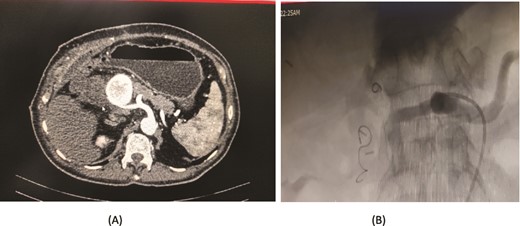

A 76-year-old male underwent distal gastrectomy with D2 lymph node dissection for gastric cancer. On the 27th postoperative day, he developed massive upper gastrointestinal (UGI) bleeding, which was confirmed by an upper gastrointestinal endoscopy (UGIE) showing large clots. A contrast-enhanced CT angiogram revealed a pseudoaneurysm arising from the common hepatic artery (CHA) and proper hepatic artery (HA). Angioembolization was promptly performed using two coils, successfully controlling the bleeding. Despite this intervention, the patient experienced re-bleeding 12 days later. Repeat UGIE again demonstrated massive clots, and CT angiography confirmed the presence of a pseudoaneurysm at the CHA. A second angioembolization was conducted using four coils, which successfully halted the bleeding. The patient’s condition stabilized, and he was closely monitored with no further complications noted (Fig. 5).

Case 5. (A) Angiogram shows a pseudoaneurysm at common hepatic artery and another at hepatic artery proper. (B) Common hepatic artery was selected and embolization performed with two coils and gelfoam